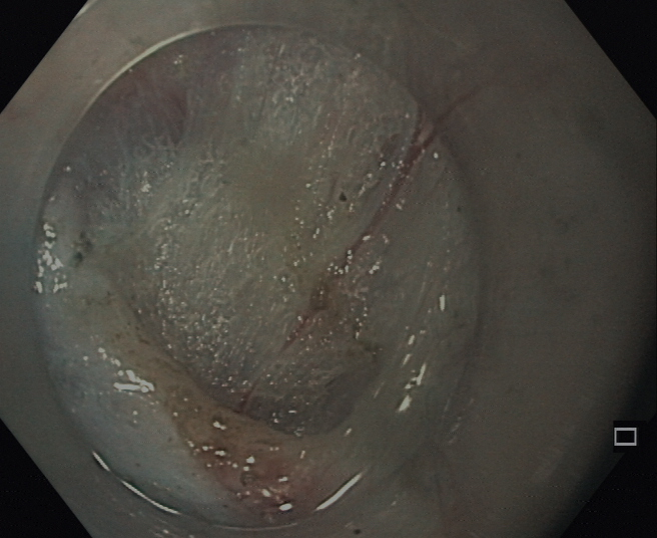

Die Endoskopische Retrograde Cholangio-Pankreatographie (ERCP) ist eine Untersuchung der Gallen - und Bauchspeicheldrüsengänge mit Hilfe eines Endoskops und einer Röntgenuntersuchung. Das Endoskop wird bis in den Zwölffingerdarm eingeführt. Über das Endoskop wird ein dünner Plastikkatheter in die Mündung des Gallengangs und/oder Bauchspeicheldrüsengangs eingeführt (Papille) und ein Röntgenkontrastmittel eingespritzt.

Die ERCP gewährleistet eine sehr gute Feinbeurteilung und ermöglicht endoskopische Operationen anstelle chirurgischer Behandlungen (Entfernung von Gallengangssteinen, Erweiterung von Gangverengungen/Stenosen, Beseitigung von Gallengangsverschlüssen, Drainage von Bauchspeicheldrüsenzysten, Implantation von Stents). Dabei kann auch eine direkte Spiegelung des Gallenganges- (= Cholangioskopie) oder des Bauchspeicheldrüsenganges (= Pankreaticoskopie) und die Zertrümmerung von z.B. Gallengangssteinen mit Hilfe einer sog. elekrohydraulischen Sonde (= EHL) erfolgen.